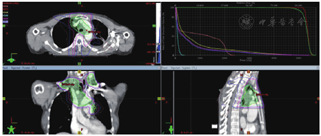

病史:患者2012年9月出现进流质饮食哽咽感,胃镜检查示:距门齿27~30cm肿物。活检示:鳞癌细胞。2012年9月24日在北京某医院行食管大部分切除、食管胃弓上吻合术,术后病理:食管溃疡型中分化鳞状细胞癌。术后分期不详,未行辅助治疗。2014年12月再次出现进食哽噎感,未诊疗。2015年3月出现声音嘶哑,就诊山东省某医院,超声检查示:双侧锁骨上、双侧腋窝淋巴结肿大。胸部CT示:食管癌纵隔、腹腔内淋巴结转移;胃镜吻合口活检:鳞状细胞癌。2015年3月30日给予吻合口、纵隔及腹膜后淋巴结IMRT 54Gy/30次,多西他赛50mg d1、8单药同步化疗1周期,序贯多西他塞60mg d1,40mg d8+顺铂20mg d1~5+西妥昔单抗500mg d1方案治疗2周期。治疗期间骨髓抑制Ⅲ度,复查CT疗效评价SD。2015年7月17日行第3周期多西他塞100mg d1,顺铂20mg d1~5方案化疗,2015年8月12日第4周期改为多西他赛100mg d1+卡铂500mg d2方案化疗1周期,治疗期间骨髓抑制Ⅲ度,胃肠道反应Ⅲ度。于2015年9月8日、2015年10月5日行多西他赛+卡铂方案2周期化疗,化疗后患者无明显不适。2015年11月下旬又出现进食阻挡感,胸部CT检查提示纵隔淋巴结转移治疗后较前进展,双侧锁骨上淋巴结转移,给予纵隔及锁骨上淋巴结精确放疗(病例22图1),1.2Gy,2次/天,共42次,92% PTV 50.4Gy,放疗后予长春瑞滨40mg d1~3+替吉奥40mg 2次/天d1~14方案化疗1周期,骨髓抑制Ⅲ度。2016年5月19日门诊复查示右肺转移(病例22图2)。既往高血压病10余年,食管癌术后血压复常。脑梗死8年余,无明显后遗症。

2.胸部CT检查 食管癌术后吻合口增厚,较前基本变化不著;纵隔淋巴结转移治疗后,较前变化不著;右肺结节灶,考虑转移。